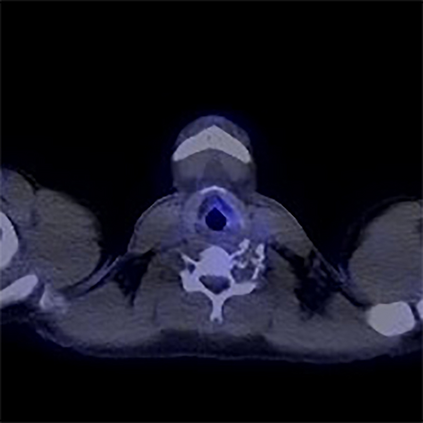

In this study, we aim to initiate the development of Radiology Foundation Model, termed as RadFM.We consider the construction of foundational models from the perspectives of data, model design, and evaluation thoroughly. Our contribution can be concluded as follows: (i), we construct a large-scale Medical Multi-modal Dataset, MedMD, consisting of 16M 2D and 3D medical scans. To the best of our knowledge, this is the first multi-modal dataset containing 3D medical scans. (ii), We propose an architecture that enables visually conditioned generative pre-training, allowing for the integration of text input interleaved with 2D or 3D medical scans to generate response for diverse radiologic tasks. The model was initially pre-trained on MedMD and subsequently domain-specific fine-tuned on RadMD, a radiologic cleaned version of MedMD, containing 3M radiologic visual-language pairs. (iii), we propose a new evaluation benchmark that comprises five tasks, aiming to comprehensively assess the capability of foundation models in handling practical clinical problems. Our experimental results confirm that RadFM significantly outperforms existing multi-modal foundation models. The codes, data, and model checkpoint will all be made publicly available to promote further research and development in the field.